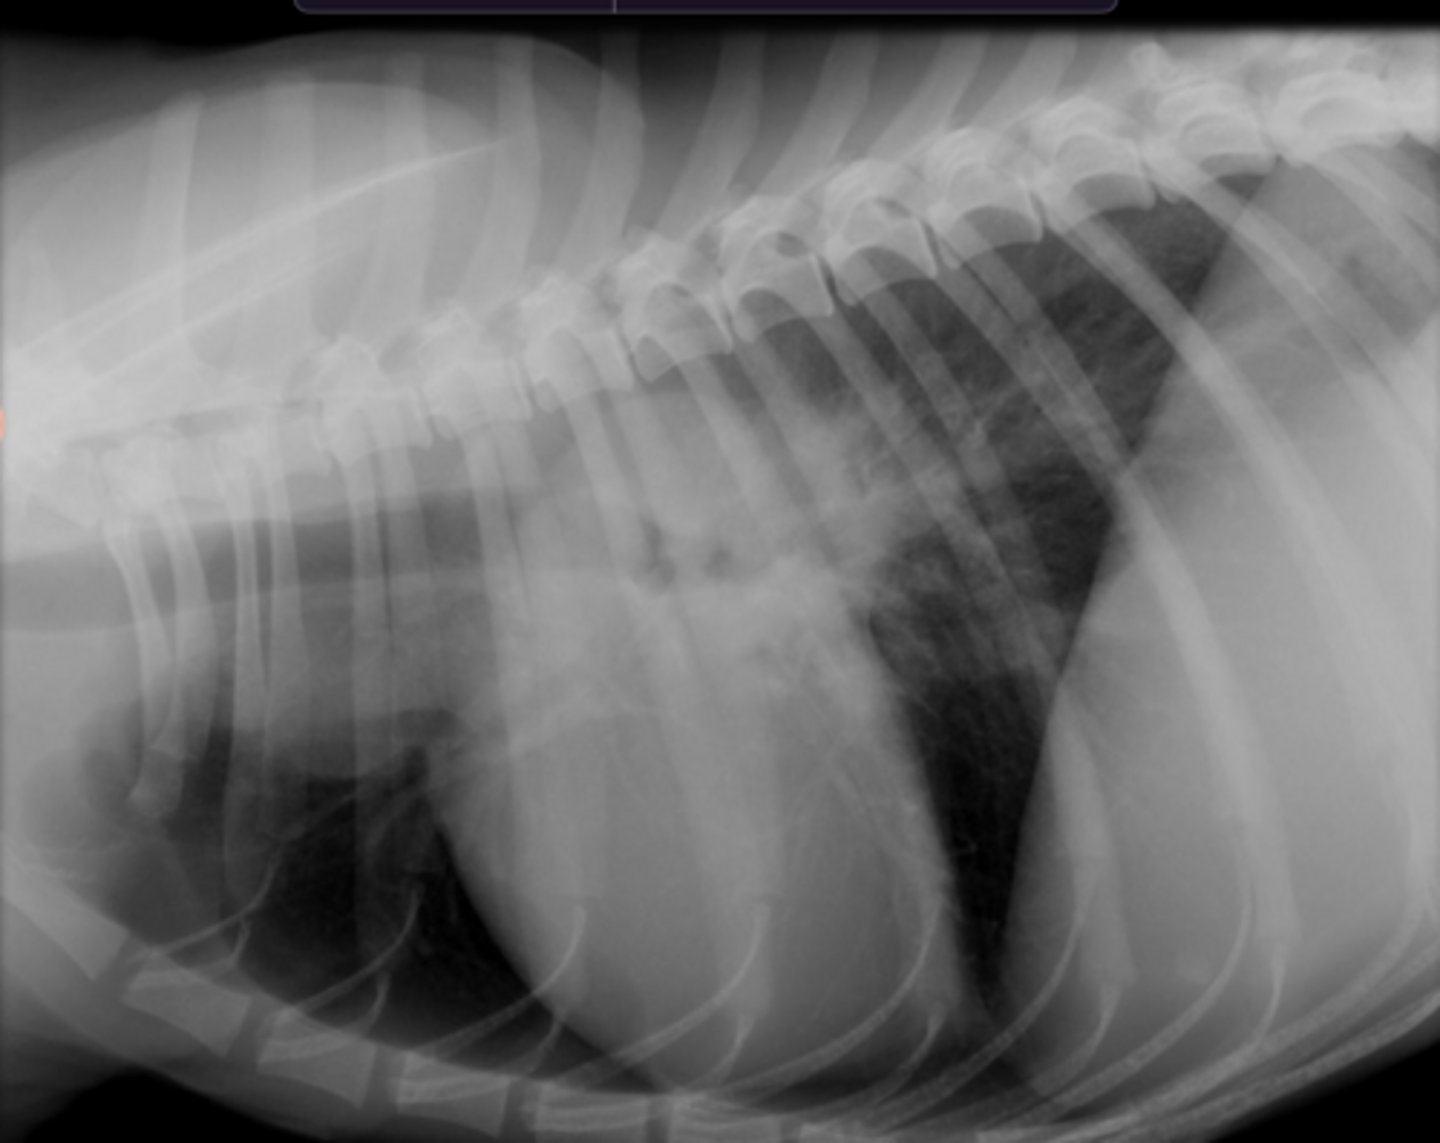

5.7 + 4.3 = 10

(K9 - 10.5)

Given the following radiograph do we have an enlarged heart?

No